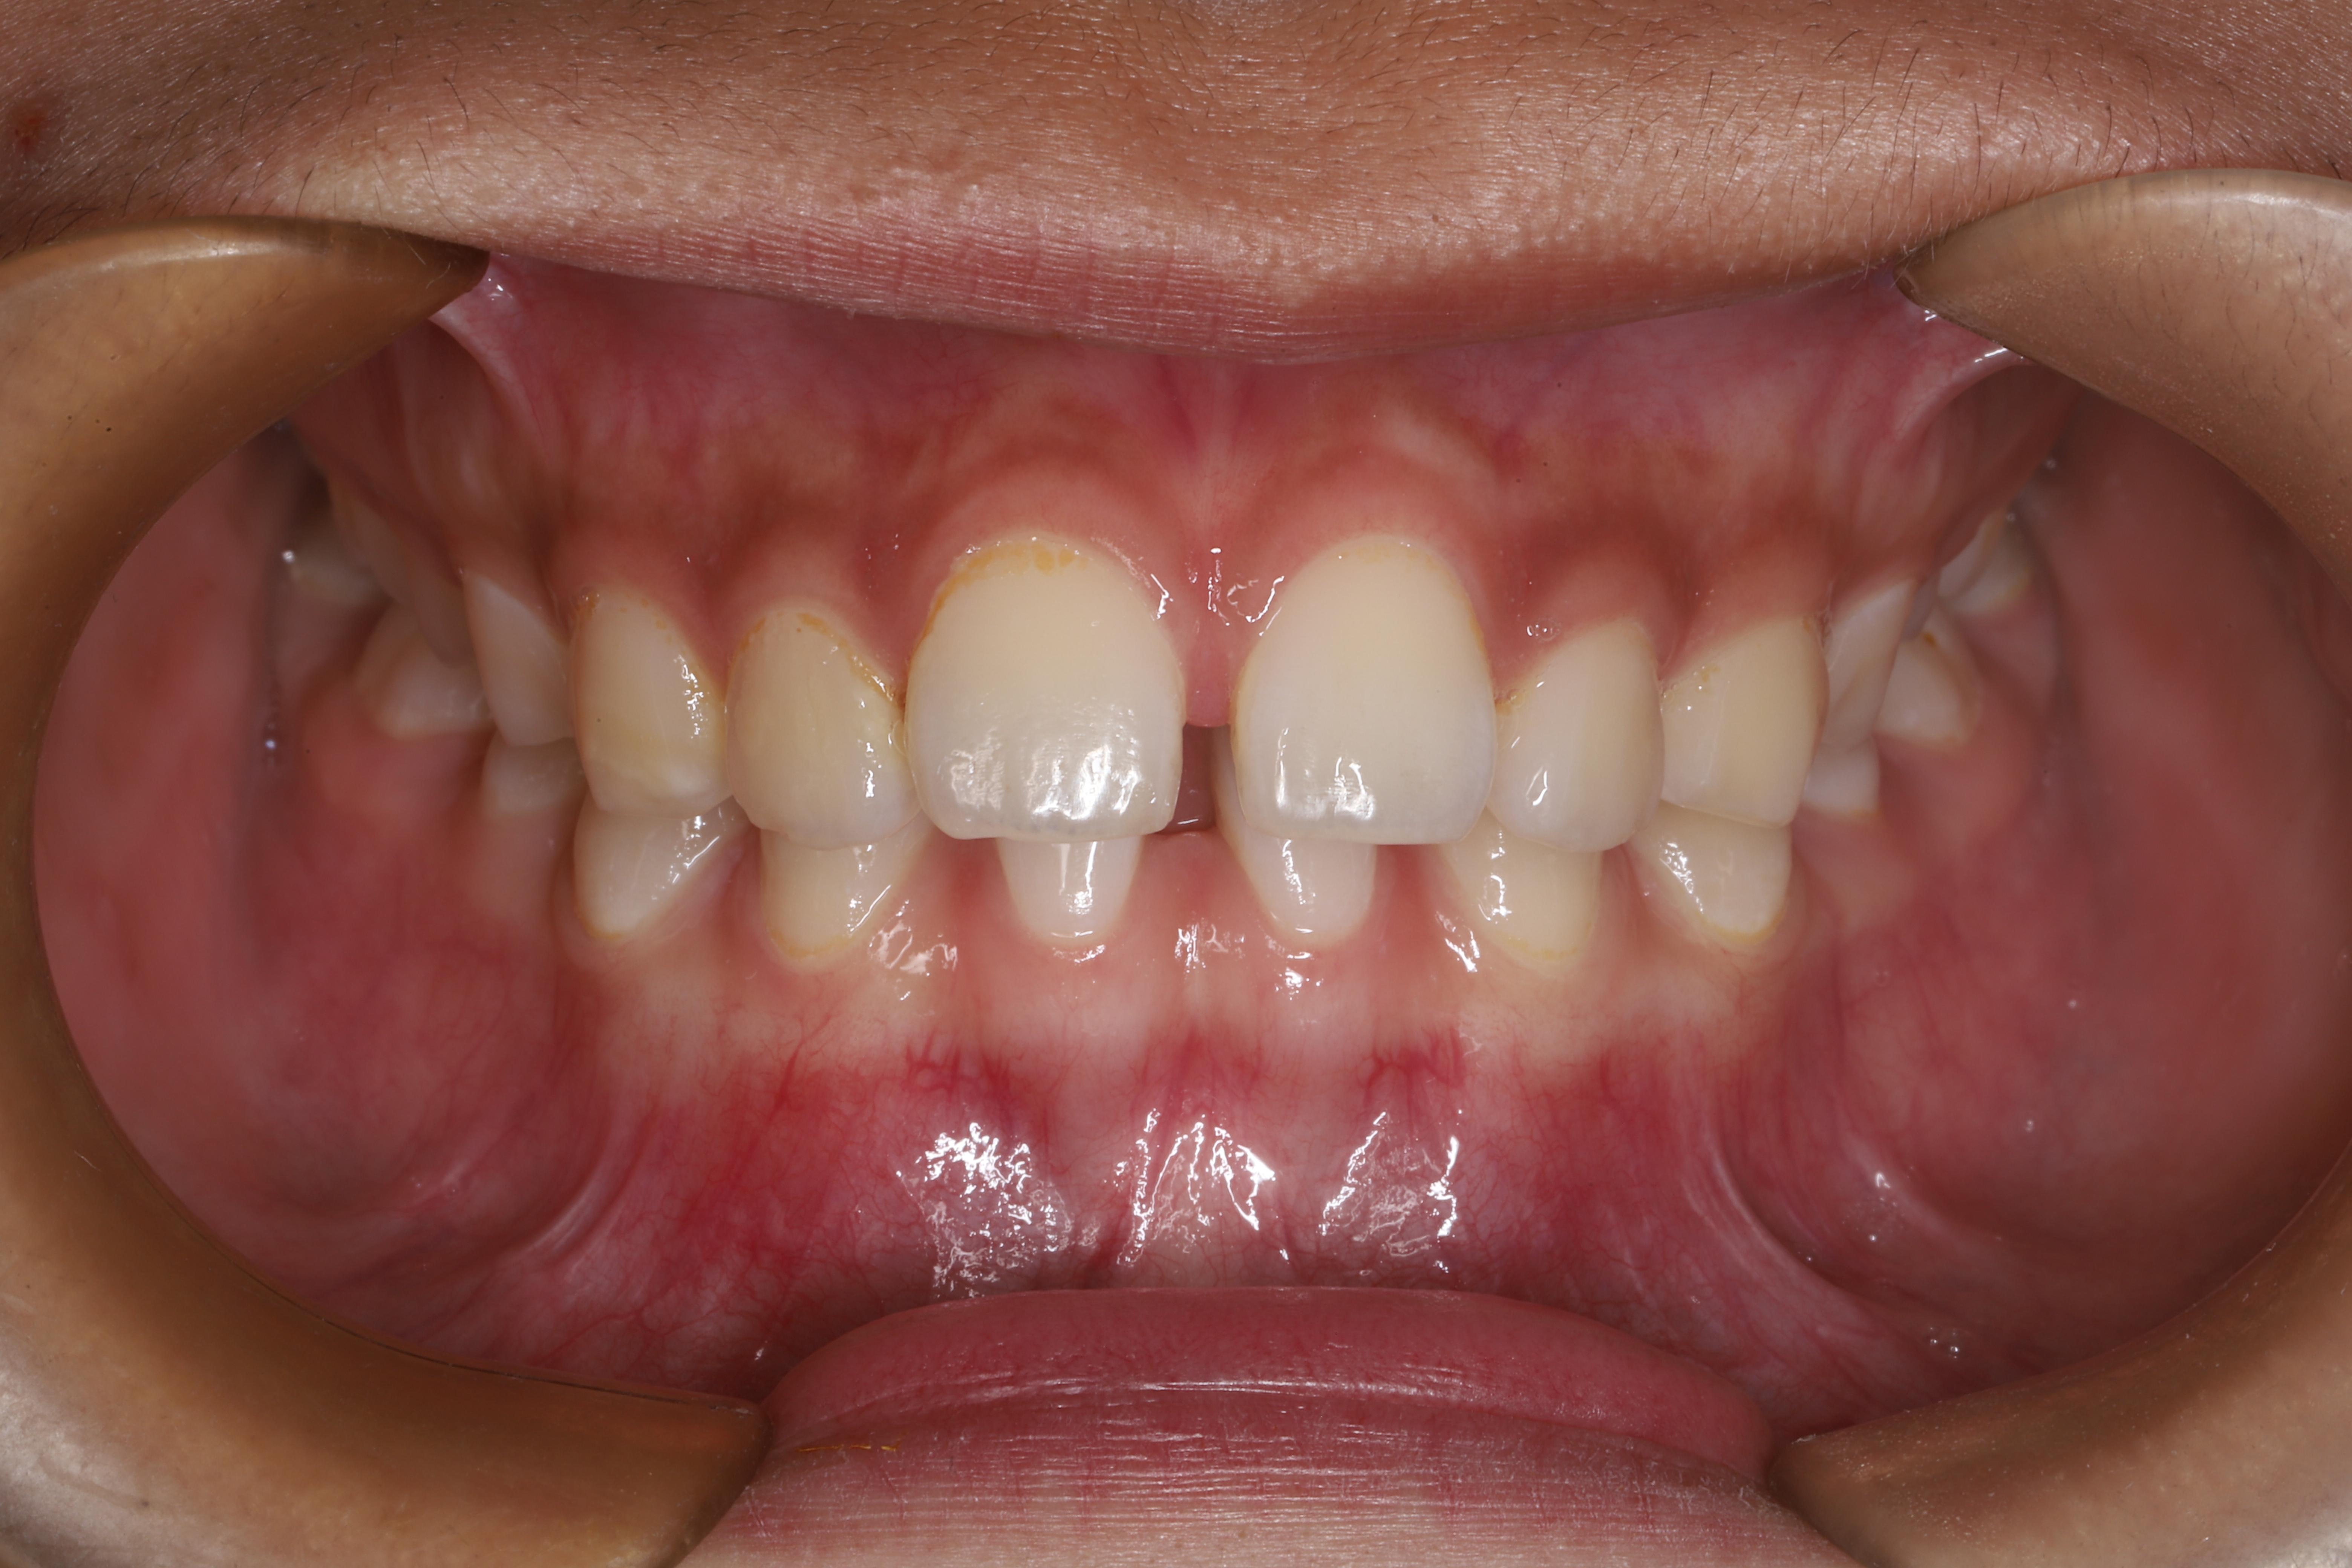

关于儿童牙齿矫正那些事(图10)

龅牙

关于儿童牙齿矫正那些事(图11)

小下巴

比如像我们经常说的龅牙、小下巴等,或者刚才提到的反颌这一类情况就需要进行早期干预。对于替牙期下颌后缩(俗称“小下巴”)或者上颌发育不足(俗称“地包天”)等需要进行矫正治疗的小朋友来说,我们建议在颌骨发育的一个生长高峰期,也就是替牙期8-10岁的时候进行正畸治疗,此阶段不仅能矫正牙齿,也是对面型的一个改善 。同时,在替牙期阶段,如发现孩子有咬唇、伸舌、前伸下颌等不良习惯,也要及时带孩子去医院找专业医师检查评估。